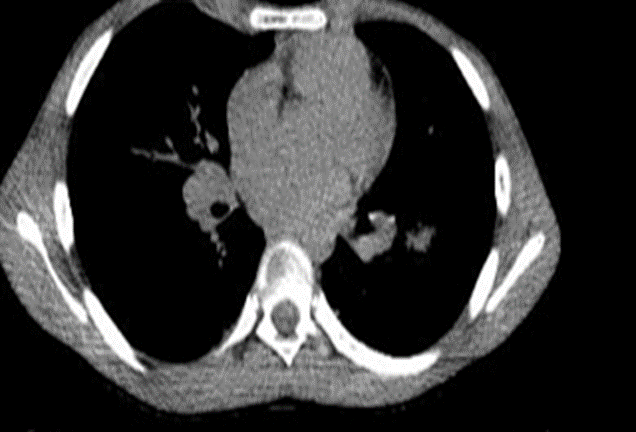

Chest CT scans displayed interest in the interstitium and alveoli, indicating dense central areas surrounded by low-density zones. There was notable pulmonary parenchymal density increase, suggesting inflammatory involvement and bilateral enlarged lymph nodes. Various other examinations were conducted, including blood tests that showed CRP 2.24 mg/dl, elevated total IgE levels (1117 IU/ml), IgG for aspergillus was positive, eosinophilia 17%, galactomannan antigen was positive (Figure 2).

Figure 2: Computed Tomography scan.